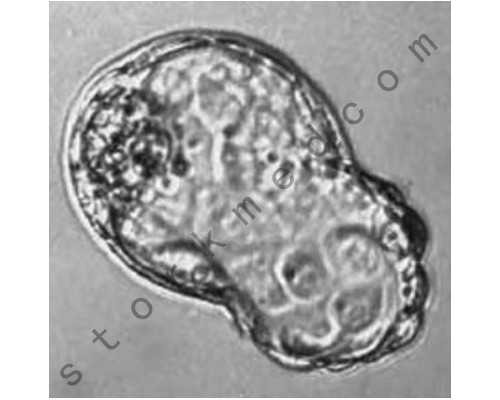

香港验血是通过抽血检测胎儿性别的医学技术,它的原理就是通过抽取母体手臂上的静脉血来提取出胎儿体内游离的DNA,再去检测它是否含有Y染色体的呢!

高中生物就学过我们的性别是由染色体种类来决定的,正常人体内有23条染色体,即人的遗传物质,而其中还有一对染色体Y和X,它们两个就是决定胎儿性别的关键所在呢!要是验血的时候验到了Y染色体,胎儿的性别就是男性啦!反之要是没验到Y染色体,那胎儿就是性别女啦!

香港验血查男女之所以对检验宝宝的性别这么有自信,同时能在准确率上达到99.8%这和它本身具有的完善的科学原理是分不开的。通过检验孕妈的血液其实就是通过血液检测其中是否含有Y染色体,我们都知道Y染色体是男性和女性性染色体的最主要区别。而性染色体又决定了宝宝的性别,所以检测过程中如果发现Y染色体,那么就一定是宝宝所含有的,因为宝妈原本体内并不存在,所以一旦检测到,就可确定宝宝是男性了。反之,检测不到,那么就是女孩儿。而检测Y染色体通常就是通过染色的方法,因为Y染色体上有一种特殊的并且能够与特定试剂发生颜色反应的基因,它被命名为"SRY"基因。它只存在于Y染色体上,所以一旦被染色并且发生颜色反应,那么宝宝就含有Y染色体,那么就可确定宝宝的性别了。

也就是说,双胞胎是从单胎而来的,所以检测双胞胎与检测单胎的原理是相同的,都是去检测母亲体内血液中的Y染色体。

但是如果怀的是双胞胎的话,当检测到Y染色体时,并不能确定一共有多少个男孩或者说全是男孩,只能确定至少有一个是男孩。

但如果没有检测到Y染色体的话,那就可以确定她们全是女孩。

科学家们通过研究发现这项技术,根据女性染色体只有X染色体,男性染色体会有Y染色体的存在。因为科学家发现了在怀孕妈妈的血液中会有Y存在,尤其在第七周浓度越来越高,这表明在怀孕第七周就可以验血查胎儿性别。因为怀孕妈妈是女性,所以不会存在Y-DNA,所以Y-DNA肯定是怀孕妈妈肚子里胎儿的。验血只要检测Y-DNA存在就可以确定是不是男孩还是女孩。如果采集怀孕妈妈的血液,在血液中检测到Y-DNA的存在,那么胎儿的性别就是男孩子,如果没有检测到,那么就是女孩子了。就这种科学的香港DNA查胎儿的准确率可以高达99.8%。